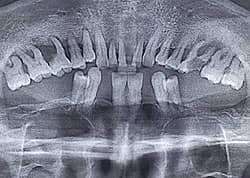

El diagnóstico se realiza sobre la base de las manifestaciones clínicas y los datos del examen instrumental del dentista. Por lo general, la enfermedad periodontal se diagnostica por casualidad, durante los exámenes médicos preventivos.